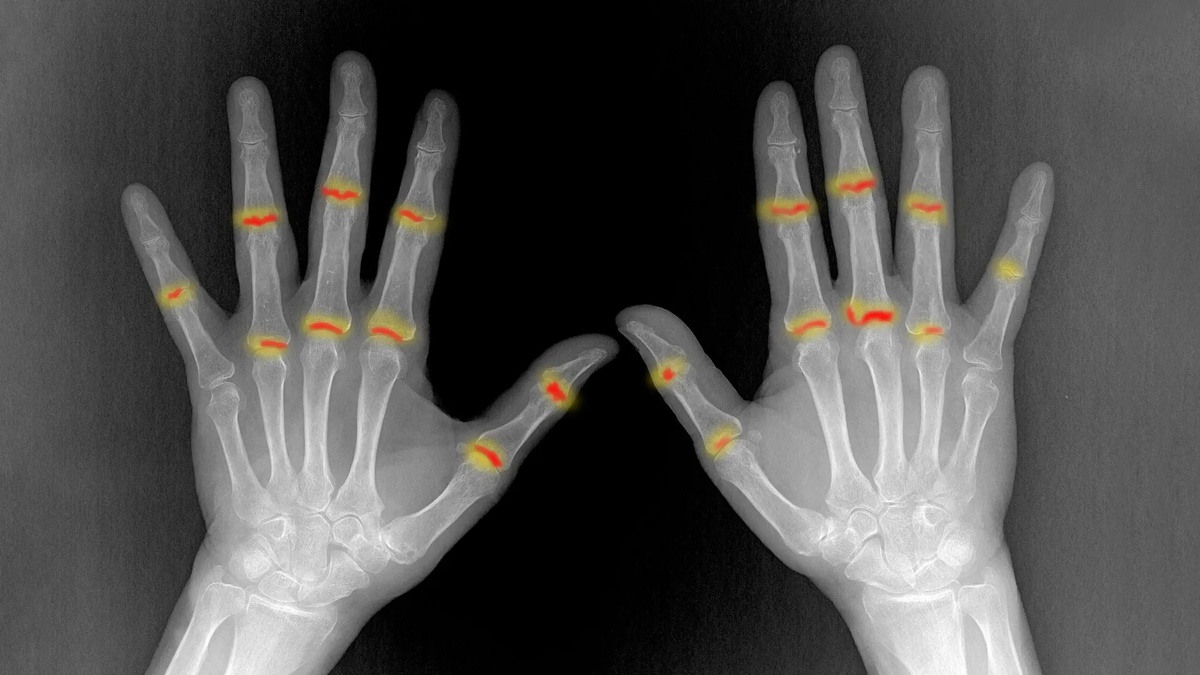

Почему обычное раздражение кожи вдруг превращается в мучительную боль в суставах? Ученые из Университета Эрлангена-Нюрнберга раскрыли тайну развития псориатического артрита. Оказывается, особые иммунные клетки-предвестники буквально совершают опасное путешествие: они покидают воспаленную кожу, проникают в кровоток и оседают в суставах 🩸. В норме наши суставы защищены клетками-фибробластами, которые работают как надежный щит. Но у некоторых пациентов эта защита ослабевает, позволяя пришельцам запустить процесс разрушения тканей. Главный прорыв исследования в том, что этих диверсантов можно обнаружить в крови задолго до первых симптомов 🦴. Это дает врачам шанс остановить болезнь в самом зародыше с помощью новой таргетной терапии, сохранив здоровье и подвижность на долгие годы. Как вы думаете, скоро ли ранняя диагностика по капле крови станет стандартом для всех скрытых болезней? 🧬